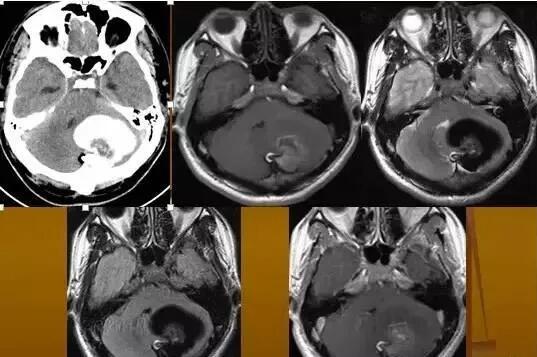

CT表現(xiàn):平掃腫瘤呈球形低密度,邊緣銳利,CT值低于腦脊液,但高于脂肪密度,看不到囊壁,無強化效應(yīng)。

MRI表現(xiàn):

皮樣囊腫呈囊狀,邊界清楚,在T1WI上呈高信號,T2WI亦為高信號,但信號強度較低。由于其內(nèi)含有毛發(fā)等不同成分,信號可不均勻,以T2WI為著。

脂肪抑制像可見高信號消失,增強掃描病灶無明顯強化,部分囊壁可見強化。皮樣囊腫破裂后,病灶與周圍組織分界欠清,蛛網(wǎng)膜下腔或腦室內(nèi)可見脂肪信號影,腦室內(nèi)脂液界面可見化學(xué)位移偽影。較小的皮樣囊腫破裂因其內(nèi)容物外溢而塌陷閉塞。